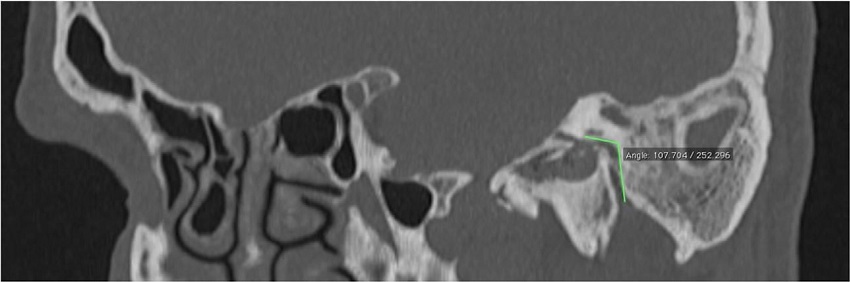

The Digital Imaging and Communications in Medicine (DICOM) files were retrieved from the Picture Archiving and Communication System (PACS) and transferred to the workstation for review; all measurements were done digitally by an experienced radiologist (A.T.S). All patients had preoperative temporal MDCT images taken. Temporal MDCT images with insufficient image quality were not included the study. Reformatted sagittal images were obtained from the thin-section axial MDCT images (Fig. 1A and B). Parallel lines from the tympanic and mastoid segments of the facial nerve were drawn in sagittal reformatted images as shown in the study of Hasaballah et al.8 Then, the angle at the second genu of the facial canal of all patients was measured (Fig. 2).

The mean angle at the second genu of the facial nerve in Groups 1 and 2 were 117.8º ± 9.63º and 114º ± 9.9º, respectively. There was a statistically significant difference between the mean angles for the two groups (p = 0.04) (Table 3).

The first part of the facial canal is the labyrinthine segment of the nerve. It extends from the fundus of the internal auditory canal to the geniculate ganglion. At this level, the direction of the nerve reverses itself, executing a hairpin turn so that it runs posteriorly. This is the ‘first turn’ of the facial nerve. The second part of the facial nerve is the tympanic segment which runs posterior-superior to the cochleariform process, superior and lateral to the oval window, and then continues inferior to the lateral semicircular canal. At the pyramidal process, the tympanic segment turns inferiorly at a 95º-125º angle (at the second genu) to become the mastoid or vertical segment.9,10 Hasaballah et al. evaluated the facial nerve course in a study of patients with cochlear implants.8 In these patients, the mean angle at the second genu was found to be 105.8º ± 13.2º. Yadav et al. examined the anatomy of the tympanomastoid segment of the facial nerve in 25 adult human wet cadaveric temporal bones under a microscope.15 They reported the angle at the second genu between the tympanic and mastoid segment to be 110º in 64%, 95º in 32% and 125º in 4% of the specimens. In our study, the angle at the second genu was measured in the oblique sagittal sections of the temporal MDCT as shown by Hasaballah and colleagues. The mean angle at the second genu in patients with and without facial canal dehiscence was 117.8º ± 9.63º and 114º ± 9.9º, respectively. Also, there was a statistically significant difference between the mean angles of the two groups. When the two groups were statistically analyzed, the angle at the second genu was found to be significantly higher in patients with dehiscent facial canals.